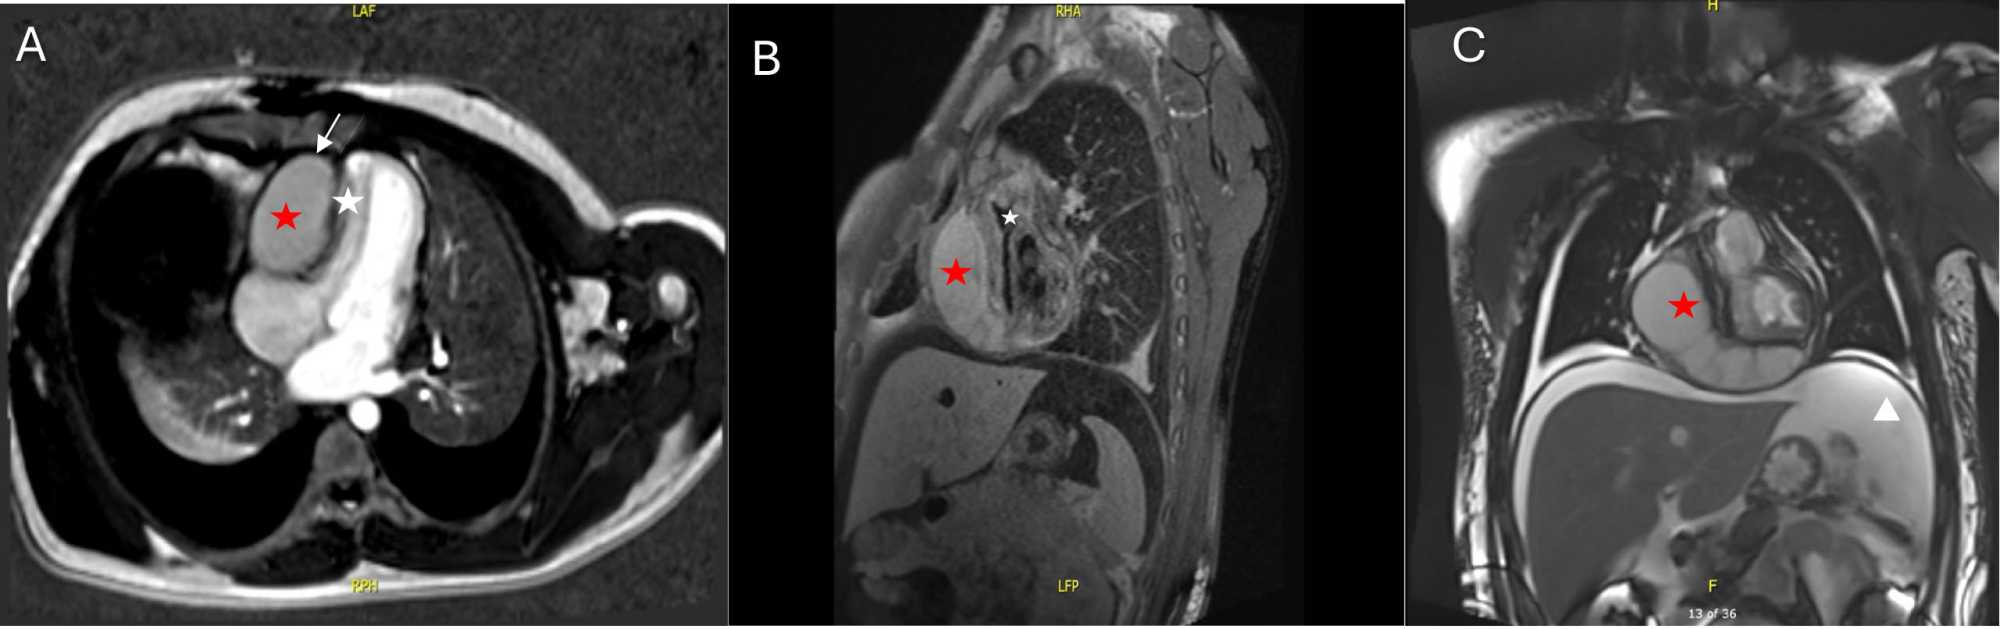

Cardiac MRI was done to determine the anatomical details of the cyst further and to distinguish its origin (pericardial vs pleural). It confirmed a cystic mass as a huge pericardial cyst. It was a capsulated fluid within the pericardium, lateral to the free wall of the RV, extending anterior to the cardiac apex. No septation was seen. Left ventricular function was reduced with an EF of 39%. Septal bouncing was seen. Right ventricular volume was reduced and its function was normal (Figure 3).

Figure 3. Panel (A-C) Cardiac magnetic resonance imaging (CMR). Red stars in all images shows the pericardial cyst. Panel (A) Early phase gadolinium enhanced MRI of the four chamber view showing compressed and slit like right ventricle (white star). Enhnacement of both visceral and parietal pericardium surrounding the capsule of the cyst (white arrows). Panel (B) midventricular short axis-view showing severely compressed right ventricle (white star). Panel (C) coronal view showing abdominal ascites (white arrowhead).